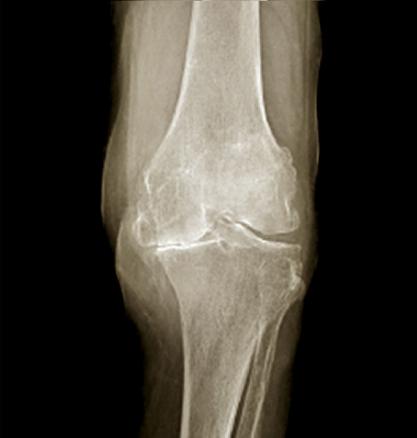

Radiographie du genou de bface